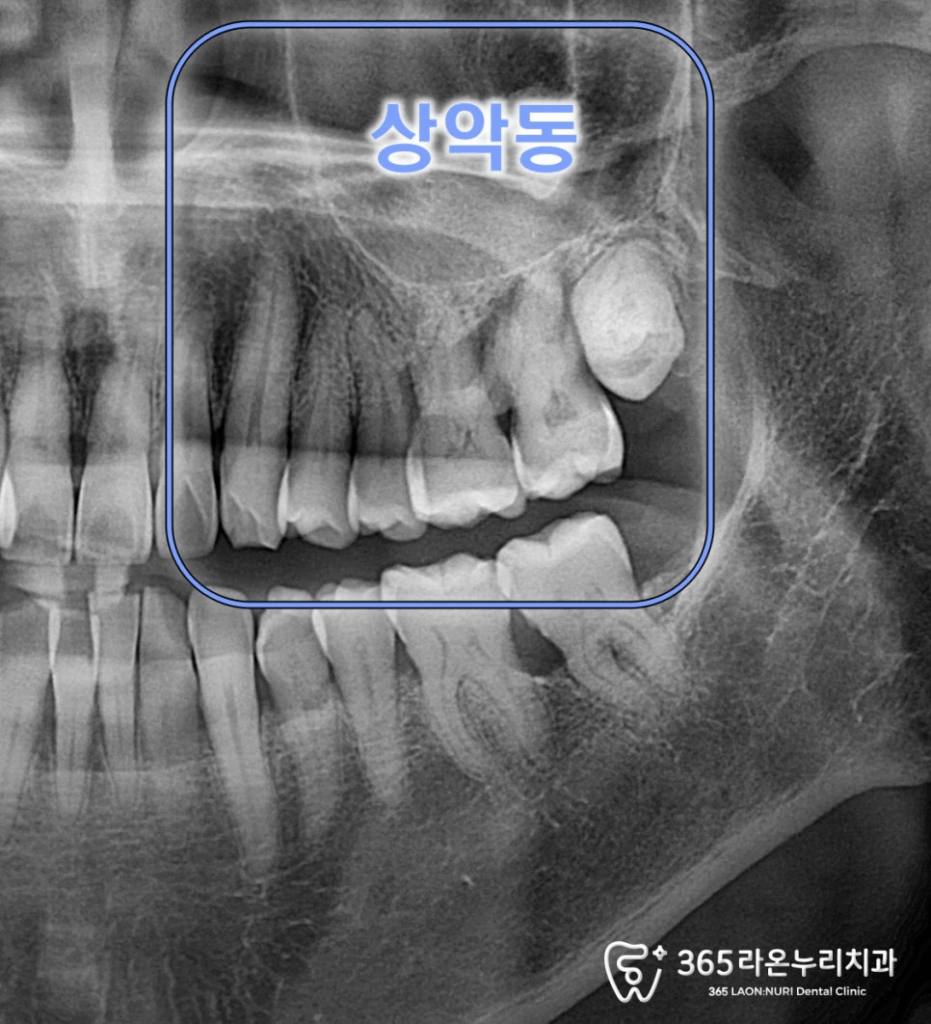

세교동 치과 에서

엑스레이를 보면

상악동이 내려 앉아있고,

염증으로 치조골이

녹아있는 상태였습니다.

남아있는 잔존 뼈가

얼마 없는 것을 볼 수 있습니다.